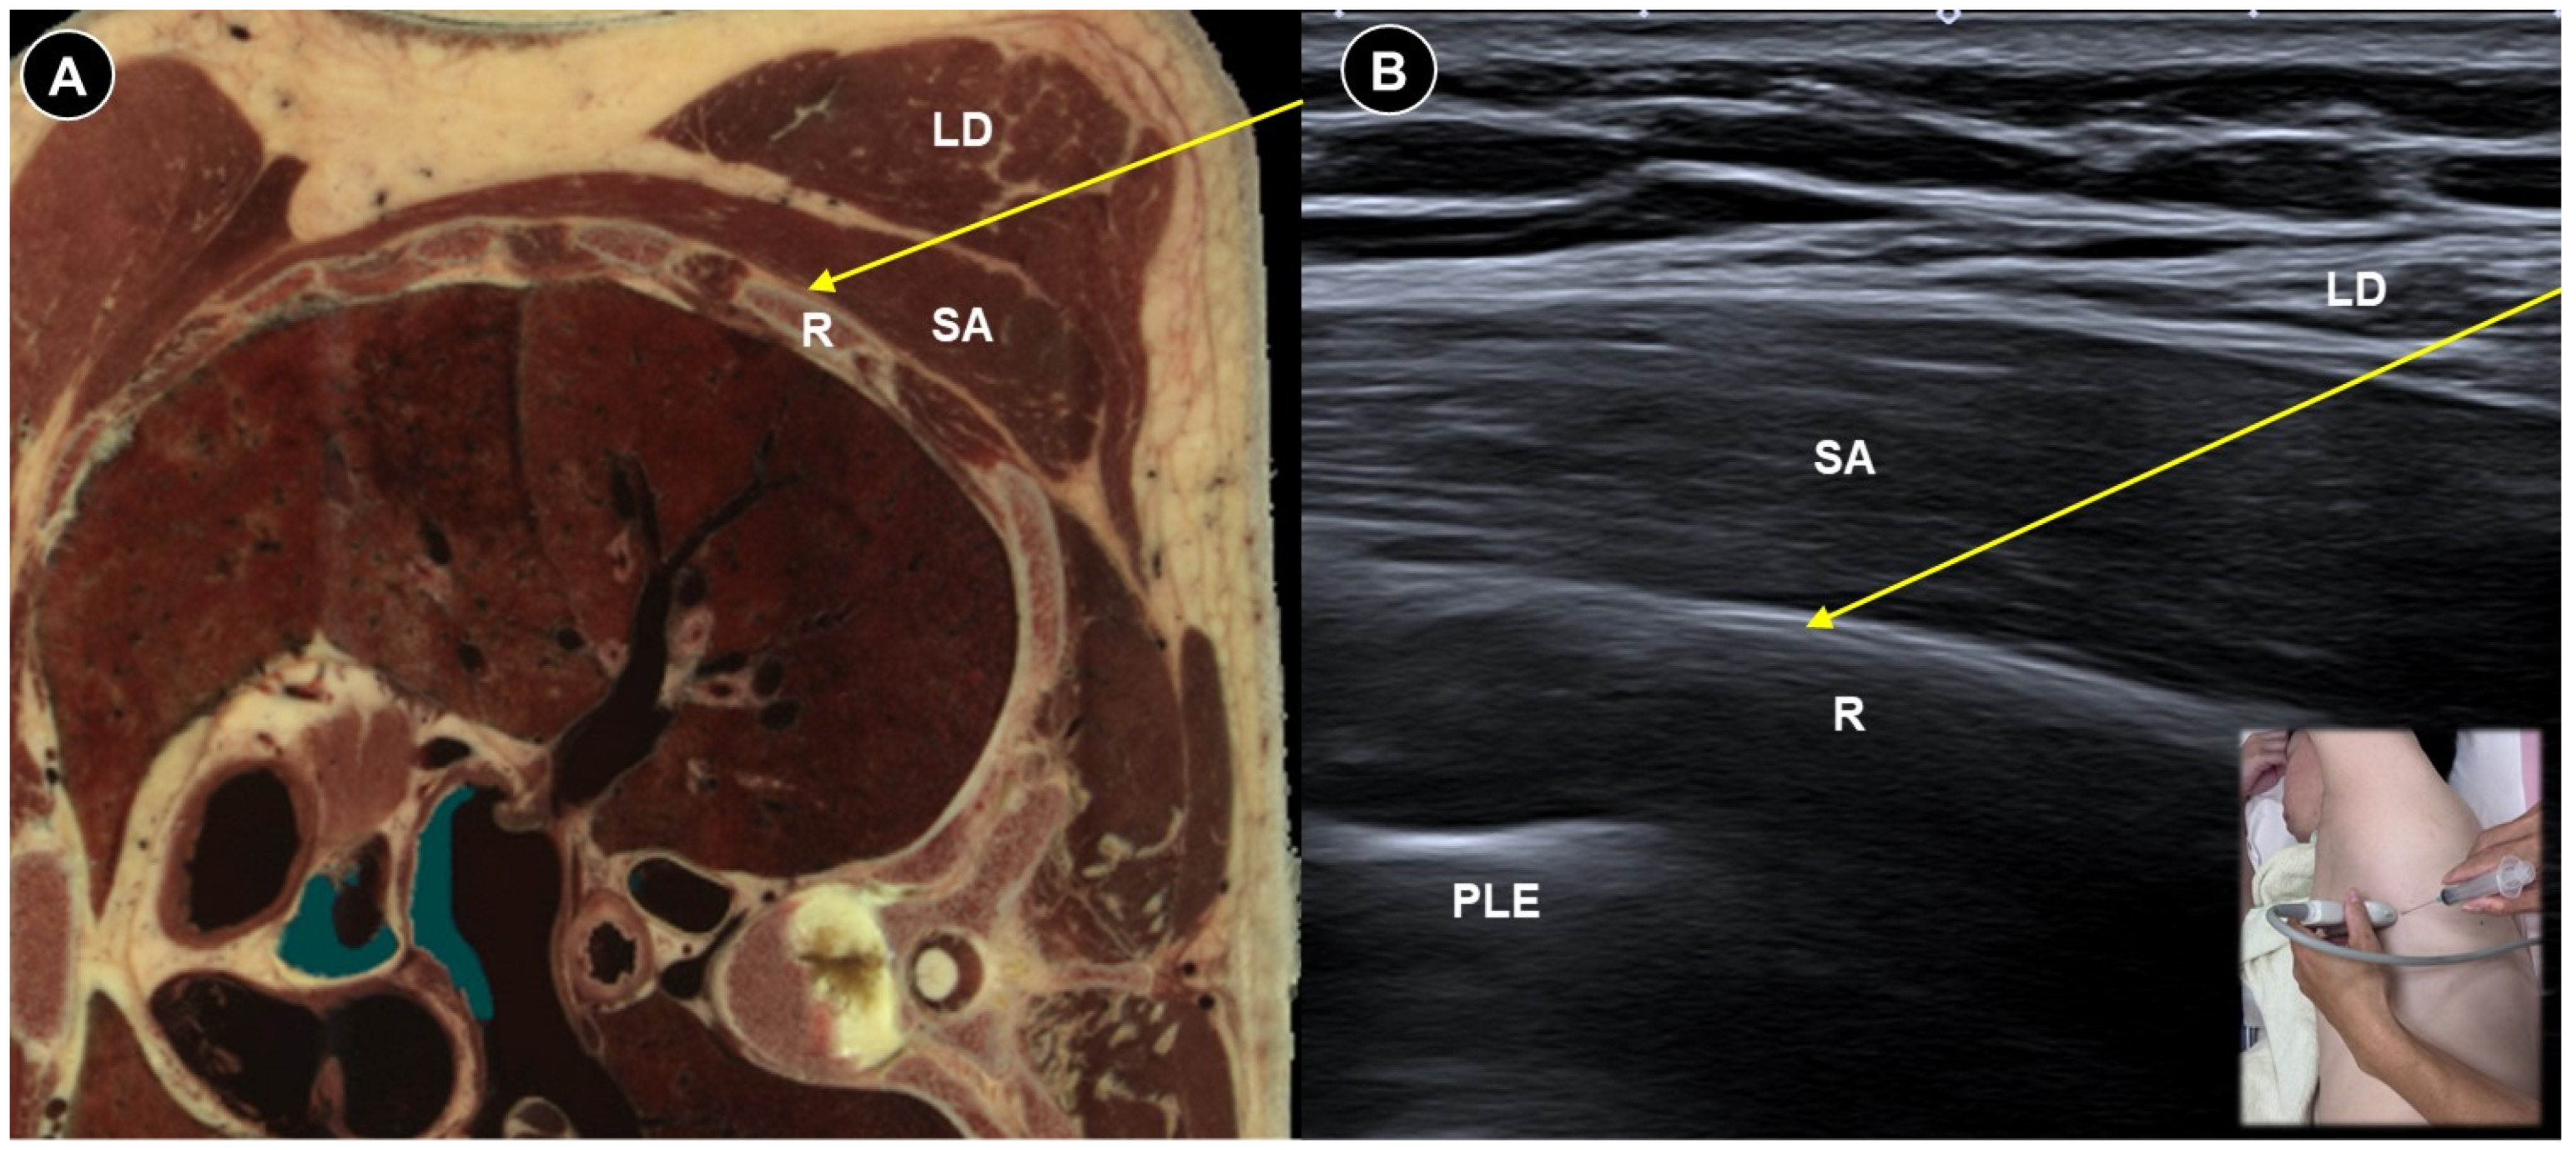

- Rahimzadeh, P.; Imani, F.; Faiz, S.H.R.; Boroujeni, B.V. Impact of the ultrasound-guided serratus anterior plane block on post-mastectomy pain: A randomised clinical study. Turk. J. Anaesthesiol. Reanim. 2018, 46, 388. [Google Scholar] [CrossRef] [PubMed]

- Liu, Q.; Khanna, A.; Stubblefield, M.D.; Yue, G.H.; Allexandre, D. Ultrasound-guided superficial serratus plane block for persistent post-mastectomy pain: Four case reports. Support. Care Cancer 2022, 30, 2787–2792. [Google Scholar] [CrossRef]